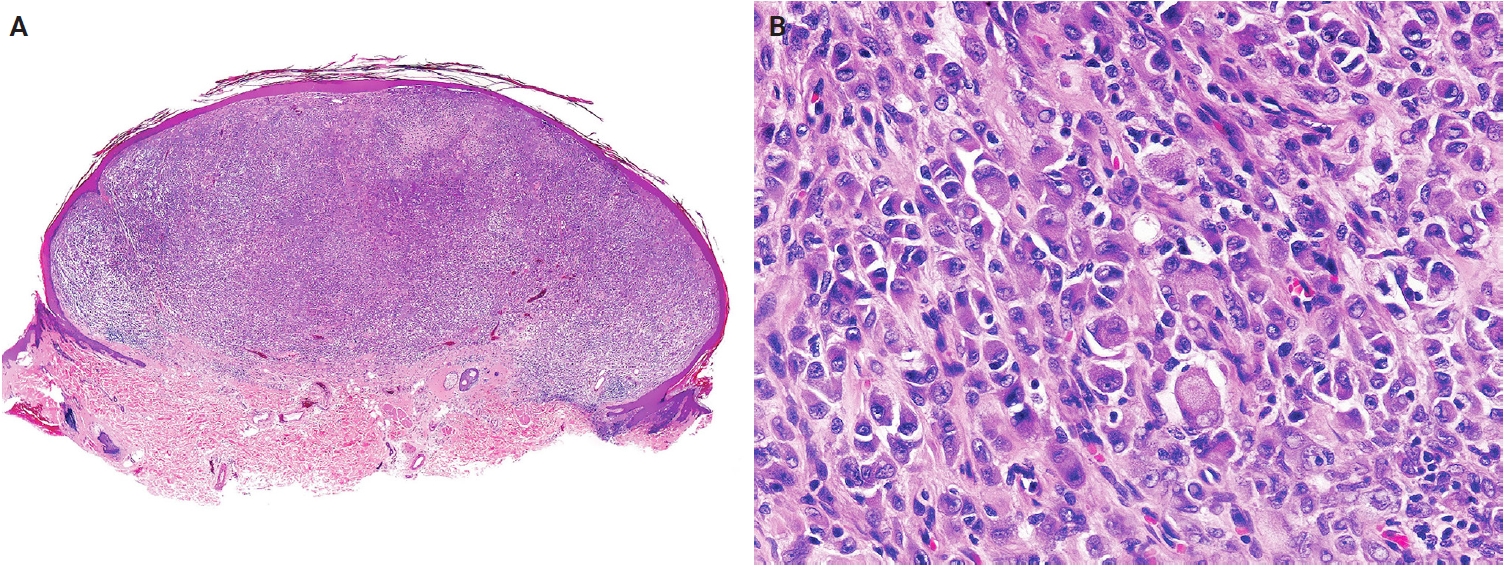

Histologically, PEComa is composed of epithelioid cells with granular, pale eosinophilic, or clear cytoplasm and round nuclei with small nucleoli (Fig. 14A, B). Most PEComas exhibit a nested or trabecular architecture with a distinctive perivascular growth pattern. Mixed epithelioid-spindle cell morphology and scattered multinucleated cells may occur; however, mitoses are generally rare. Most reported cases of cutaneous PEComa lack malignant features, such as marked pleomorphism, high mitotic activity, and necrosis [292-296]. Malignant primary cutaneous PEComas are exceedingly rare [290,297]. Currently, cutaneous angiomyolipomas are classified as hamartomatous or lipomatous neoplasms with smooth muscle elements, rather than true PEComas. Immunohistochemically, PEComas coexpress melanocytic markers (e.g., human melanoma black 45 [HMB-45], melan-A (MART1), microphthalmia-associated transcription factor [MITF]) and muscle markers (e.g., SMA, desmin, caldesmon) [298,299].

Fig. 14.

Perivascular epithelioid cell tumor. (A) The tumor shows dermal epithelioid cells arranged in a trabecular and nested growth pattern. (B) The tumor cells display round to oval nuclei with fine chromatin and abundant clear to pale eosinophilic cytoplasm, with a delicate capillary network surrounding the tumor nests.